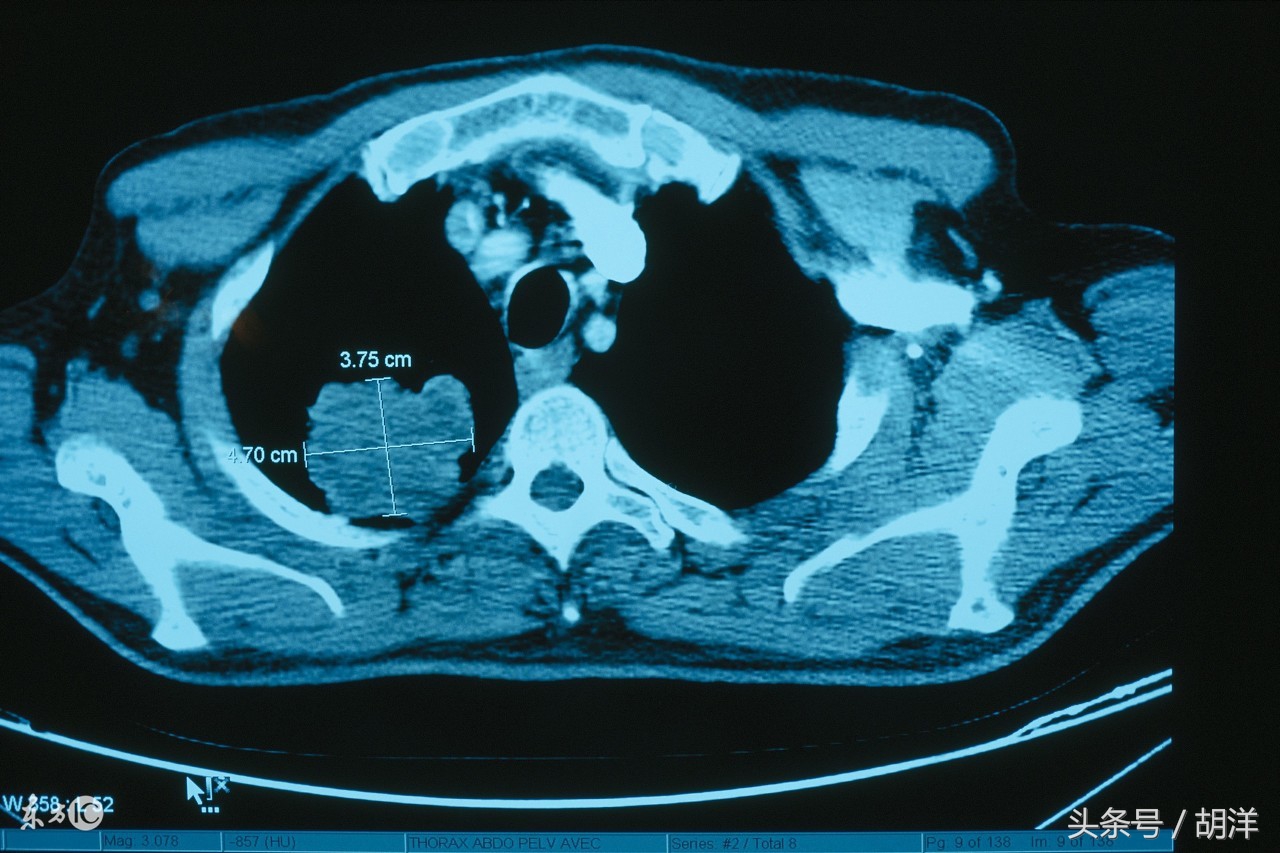

第二、骨头部位的转移

肺癌最常见的转移部位是椎骨、四肢骨、肋骨,有的时候转移到颅骨,胸骨等部位,转移灶通常会在骨头进行组织破坏,产生破骨细胞将骨头的钙质分解并破坏骨质,主要的症状是剧烈的疼痛,有时候会产生病理性骨折,即转移部位骨折磨坏严重,承受不了重力而在行走咳嗽等用力过程中骨折。